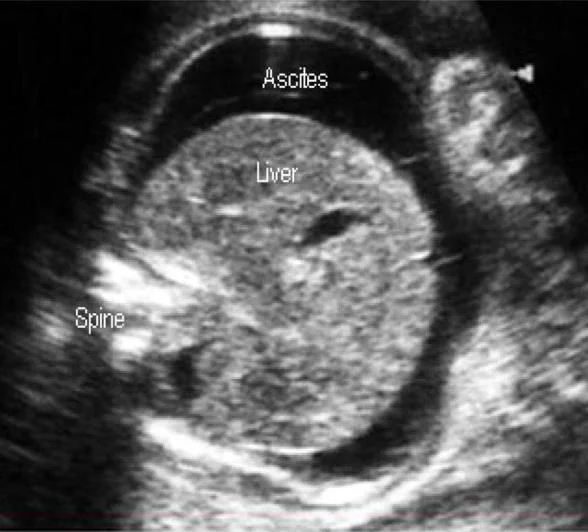

Ultrasonography

Role in Monitoring Fetal Condition

-

To Establish The Correct Gestational Age.

In Guiding Invasive Procedures And Monitoring Fetal Growth And Well-being.

Ultrasonographic Parameters To determine Fetal Anemia: * Placental Thickness. * Umbilical Vein Diameter (increased). * Hepatic Size. * Splenic Size. * Polyhydramnios. * Fetal Hydrops (e.g., Ascites, Pleural Effusions, Skin Edema). * Blood velocity (increased).